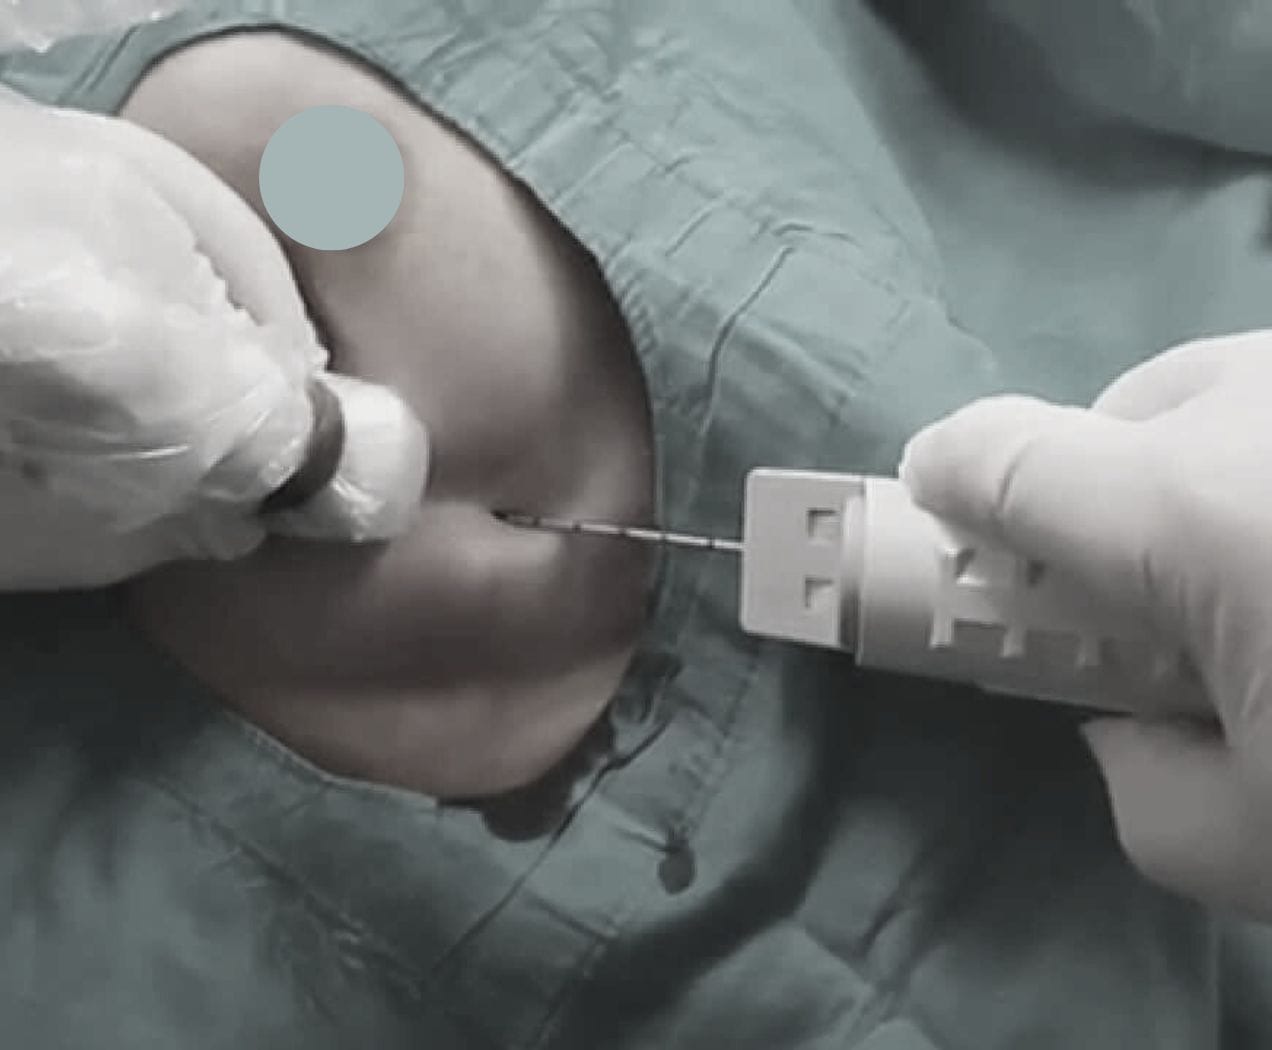

Sous Guidage Échographique : Prélèvement de cellules d'un nodule thyroïdien à l'aide d'une aiguille fine pour une analyse cytologique, déterminant la nature bénigne ou maligne du nodule.

Acte réalisé sous anesthésie locale. La durée est courte, variable selon la procédure.

Le geste est effectué sous contrôle visuel continu (Écho ou Scanner) pour une précision maximale.